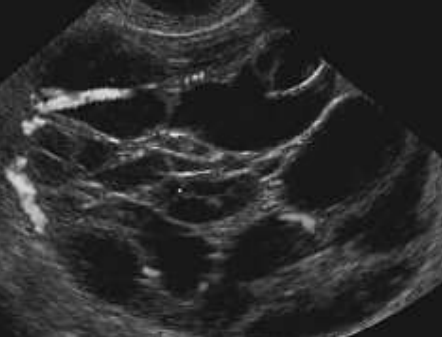

A imagem de um exame ultrassonográfico ginecológico abaixo é suspeita para: